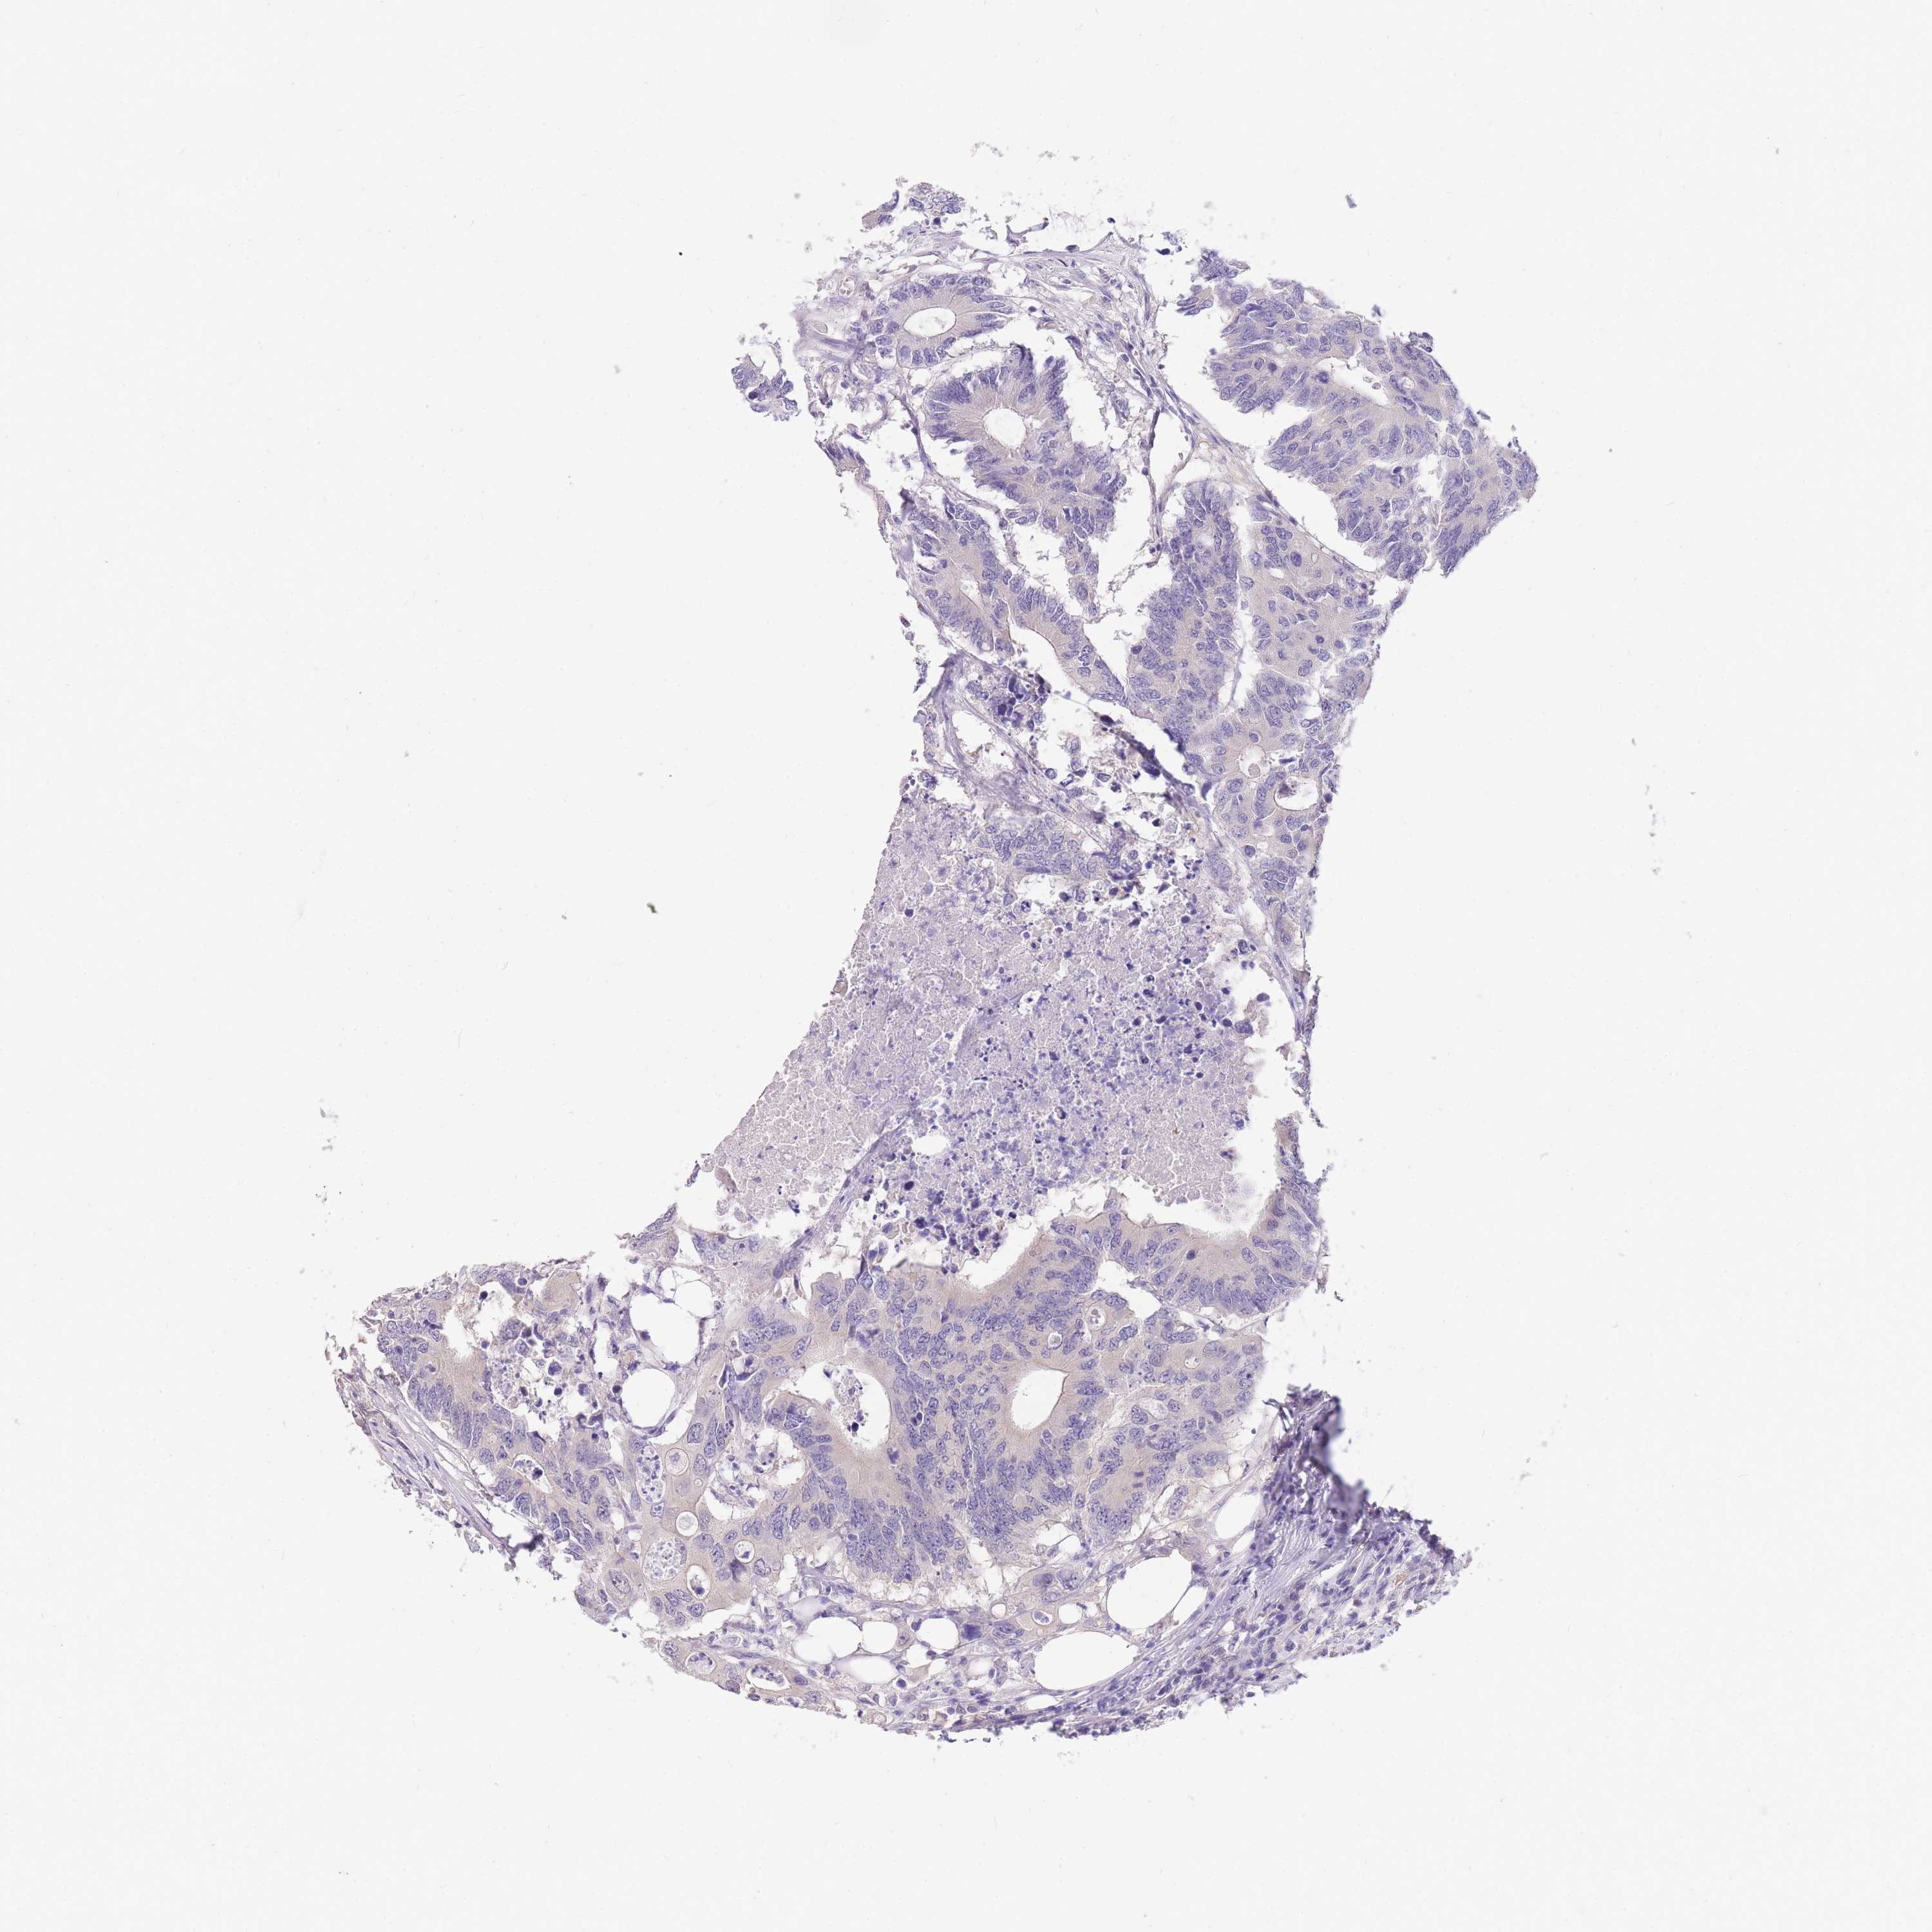

CANCER COLORECTAL CANCER Show tissue menu

Colorectal cancer

Rectum adenocarcinoma